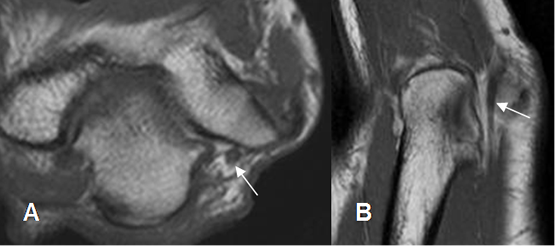

La inserción del tendón del tríceps en el olécranon, se observa mejor en secuencias sagitales. (3). Muestra estriaciones a nivel de su inserción, por interposición de grasa entre los fascículos. (8). (Fig 12 y 13). Puede encontrarse laxitud del tendón en extensión completa del codo, que no debe confundirse con ruptura y se confirma valorando las imágenes axiales. (8). (Fig 14).

Fig 13. Tendón del tríceps normal en RM.

A: RM axial en T1 y B: RM coronal en T1. Estriaciones grasas a nivel de su inserción.